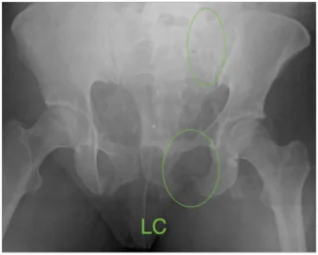

Lateral Compression (LC): look for rami fractures +/- sacral fractures

These are most commonly associated with high speed motor vehicle accidents involving lateral impact [3].

-    higher incidence of intra-cranial injuries (50%) likely due to association with high speed MVA.  Brain injury is the most likely cause of death in this patient population.

-    high incidence of concomitant lower extremity fractures and retroperitoneal hematoma

-    generally, stable LC injuries are not associated with major pelvic vascular injury